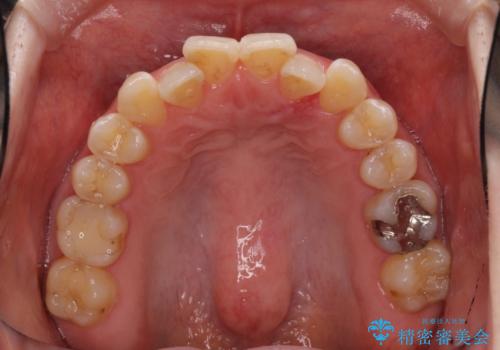

- 前歯のデコボコを治したいとのことで来院された患者様です。

上下顎ともに歯列全体の後方移動とIPR(歯と歯の間を削る)によってデコボコが解消するように設計し、インビザラインにより治療を行うこととしました。

1日22時間の装着時間をほとんど達成することができず、治療には当初予定の2倍以上の期間を要することとなりました。